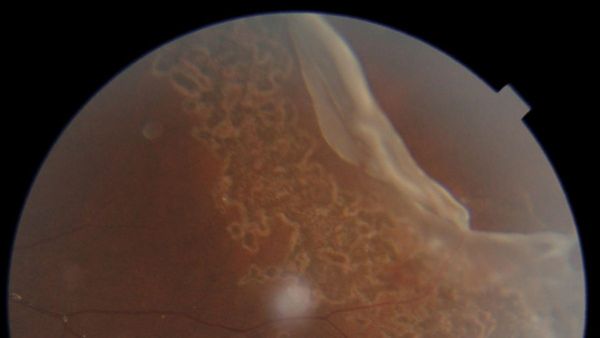

This led to the discovery of a Giant Retinal Tear, a condition that could result in irreversible vision loss if not addressed promptly. Upon referral to Aster Hospital Mankhool, Dr. Gazala Hasan Mansuri, a specialist in ophthalmology, confirmed the diagnosis through a detailed examination, including Fundus Photography and Optical Coherence Tomography (OCT).

Dr. Gazala Hasan Mansuri, emphasizing the urgency of the situation, opted for a non-invasive laser procedure to seal the tear and prevent any further damage that could lead to retinal detachment. This procedure, which took only 15-20 minutes under topical anaesthesia, involved the application of 3-4 rows of laser spots around the affected area using a 532 nm Green Laser. The child was able to go home the same day, and subsequent follow-ups confirmed the successful healing of the retinal tears, allowing him to fully recover and regain normal vision.

Giant Retinal Tears (GRTs) pose a significant threat to vision, covering more than a quarter of the retina's surface. They can lead to retinal detachment if untreated, which is a major cause of vision loss. GRTs, comprising about 1.5% of all retinal detachment cases due to tears, are challenging to manage, especially in children due to higher risks of complications such as scarring (Proliferative Vitreoretinopathy or PVR).